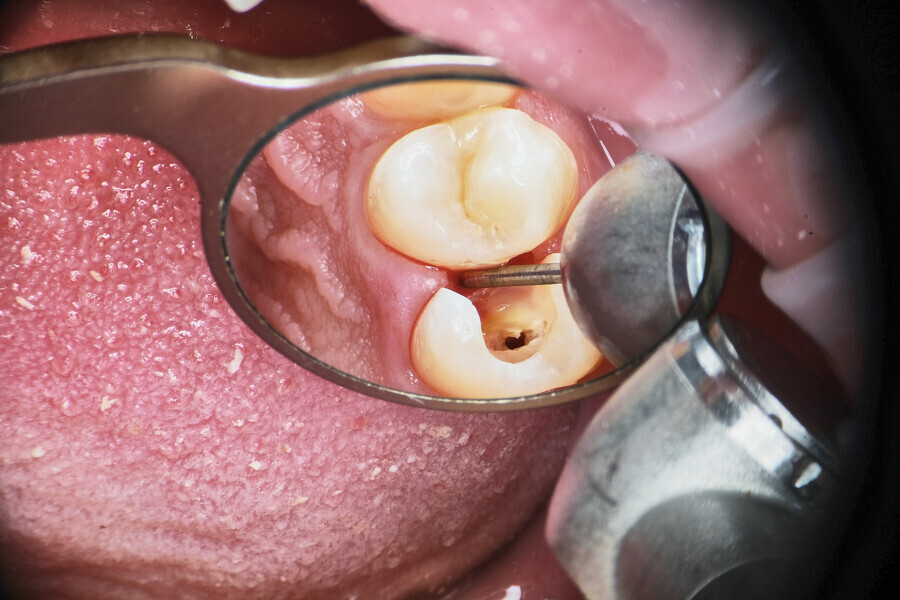

Fig. 1.

The piston technique is simple and predictable. Once the final preparation and irrigation protocol has been performed, owing to the specific properties of CSBSs, the canal should not be overdried. A small amount of moisture should remain in the canal space as the catalyst for the setting reaction of the sealer. With the application needle introduced to the maximum level of the insertion, gently eject the material from the syringe directly into the canal space. To avoid extrusion, try not to block the needle in the canal. After seeing the material in the canal space, remove the needle and use a hot gutta-percha extruder to create a plug in the coronal part. Next, push the coronal part of the gutta-percha with the cold plugger towards the apical zone. Do not push more than 1–2 mm (Fig. 1).